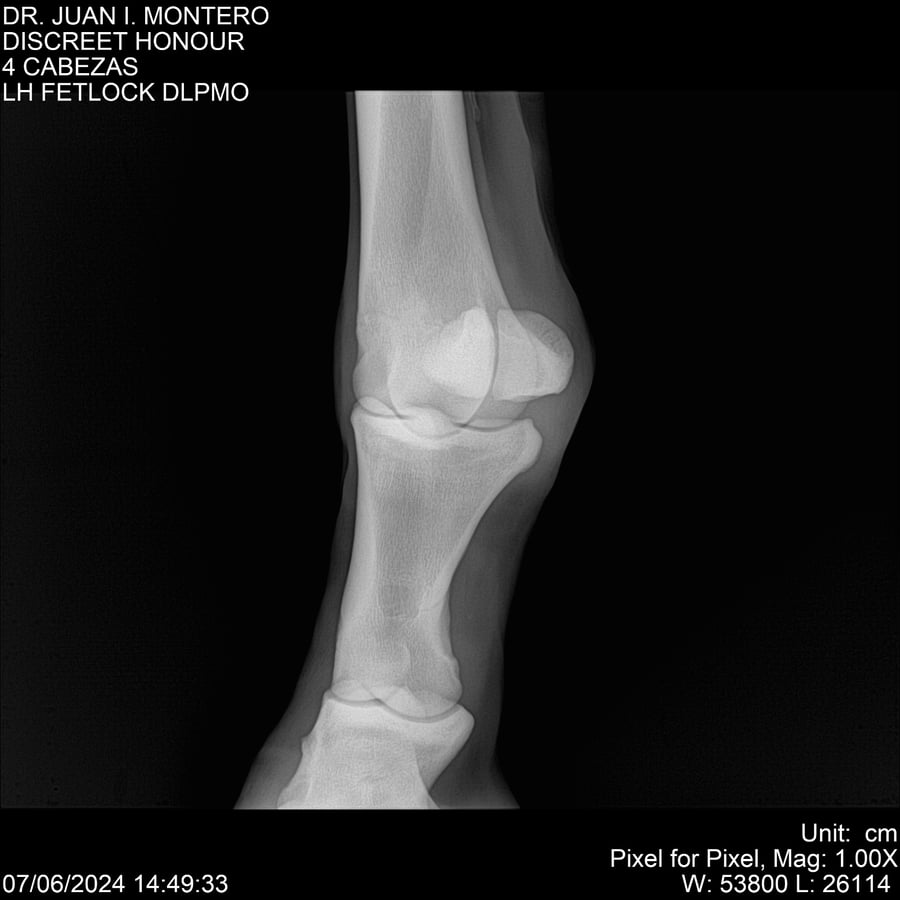

LOTE 6, DISCREET HONOUR 🔥 🔥 🔥 Lote Anterior Volver al remate Lote Siguiente Ficha Contacto Montevideo - Ficha del Lote Identificador: #281093 Categoría: Yeguarizos Montevideo - 82 Visualizaciones ClicData Contacto Empresa: Abelenda N. R., Walter Hugo Nombre*: Teléfono* : E-mail* : Mensaje Enviar Registrese gratis Este contenido Exclusivo está disponible sólo para usuarios registrados Ingresar